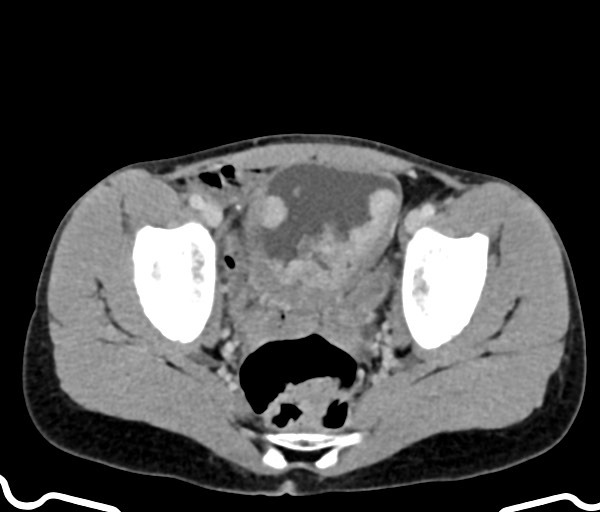

Vesicovaginal fistula:

Case courtesy of Dr Ian Bickle, Radiopaedia.org, rID: 48793